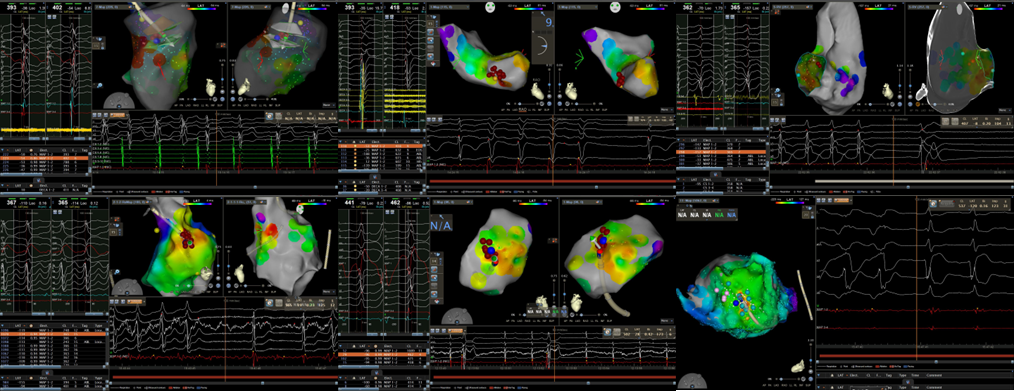

近2周,相继6例无休止室速病例经过药物及电复律治疗无效或治疗期间发生心脏停搏。我院心血管内一科起搏电生理团队在面临急诊手术高风险及高不确定因素情况下,应用急诊射频消融方式顺利终止上述患者无休止室速,改善患者血流动力学及心脏功能。

传统认知中,射频消融术只能择期进行,并且仅适用于血流动力学稳定的患者。目前,在成熟完备的标测技术和手段加持下,对血流动力学不稳定的无休止室速行急诊射频消融术能转服窦律,为后续原发疾病诊治或ICD(体内除颤器)植入争取机会。